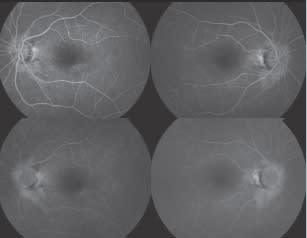

Figure 4. Fluorescein angiogram, March 2010

Figure 5. Fluorescein angiogram, January 2011